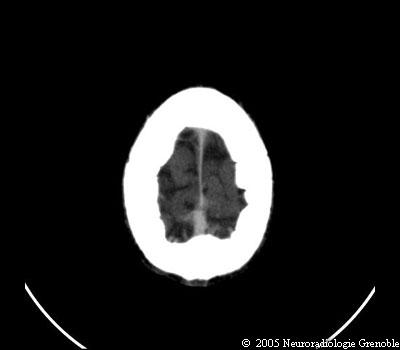

Radioanatomie TDM de l'encéphale

TDM cérébrale sans injection